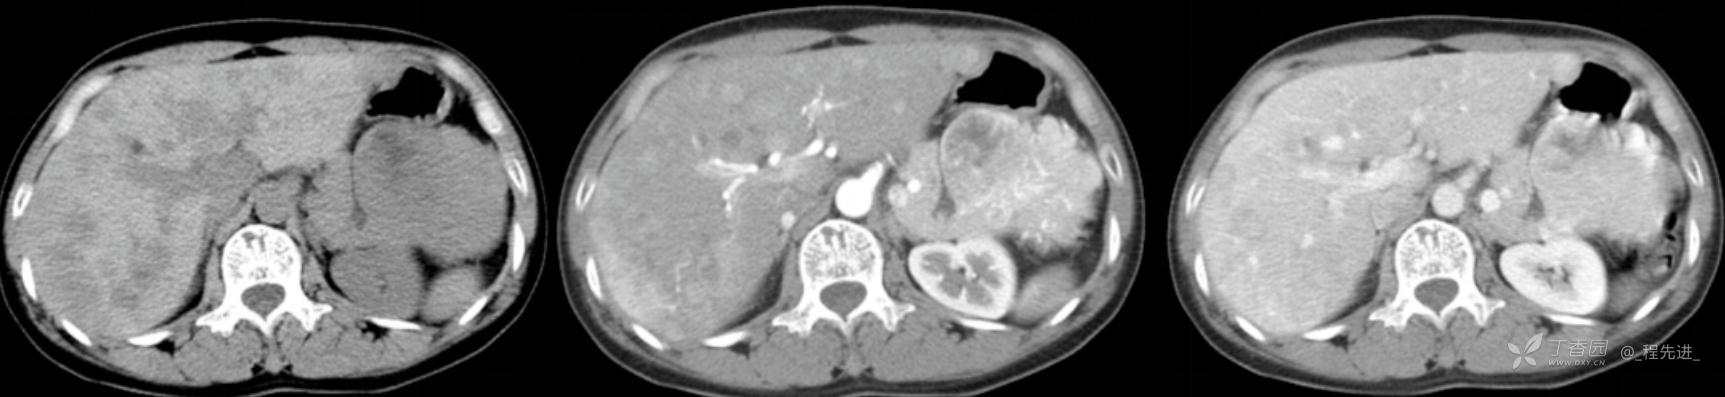

图像左边为平扫,中间的是动脉期,右边的是静脉期